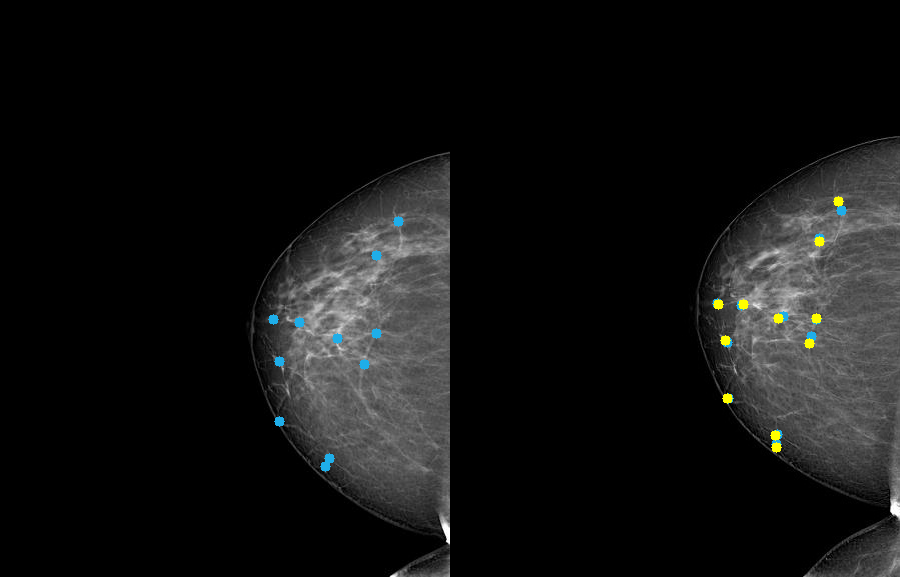

Refer to caption

Figure 5: Example of landmark annotation performed by two radiologists. Blue markers indicate landmarks placed during the initial annotation phase; yellow markers show the refined annotations from the second (validation) phase.

Annotations were generated using CVAT tool [CVAT] in two phases by two professional radiologists. Annotation protocols for both phases, including an example of what constitutes corresponding landmark locations, are available online.

During the first phase, the first annotator was asked to place 12-15 corresponding landmarks in an mammography pair that was displayed side-by-side in CVAT. This initial annotation of 100 image pairs required 31.6 hours of radiologist time. For the second phase, landmarks in the left image were fixed in place and displayed, whereas landmarks in the right one were deleted. The second annotator was then tasked with determining landmarks on the right side to the locations that they considered to match the displayed landmarks on the left side. This crucial validation phase required even more meticulous effort, taking approximately 63 hours to complete for the same set of 100 pairs. An example of landmark annotation is shown in the Figure 5.